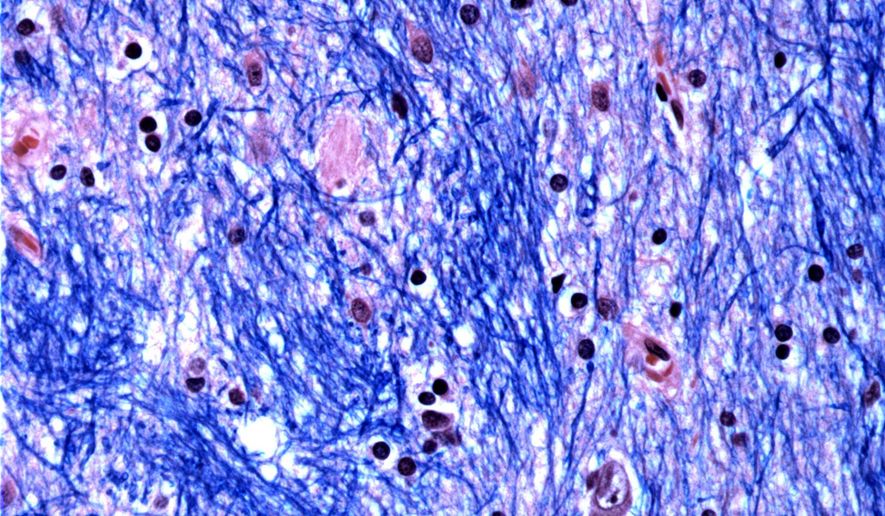

Scientists at the Broad Institute of MIT and Harvard, McLean Hospital in Massachusetts and Harvard Medical School studied brain tissue donated by 53 people with Huntington’s and 50 without it, analyzing half a million cells.

They focused on the Huntington’s mutation, which involves a stretch of DNA in a particular gene where a three-letter sequence – CAG – is repeated at least 40 times. In people without the disease this sequence is repeated just 15 to 35 times. They discovered that DNA tracts with 40 or more such “repeats” expand over time until they are hundreds of CAGs long. Once CAGs reach a threshold of about 150, certain types of neurons sicken and die.